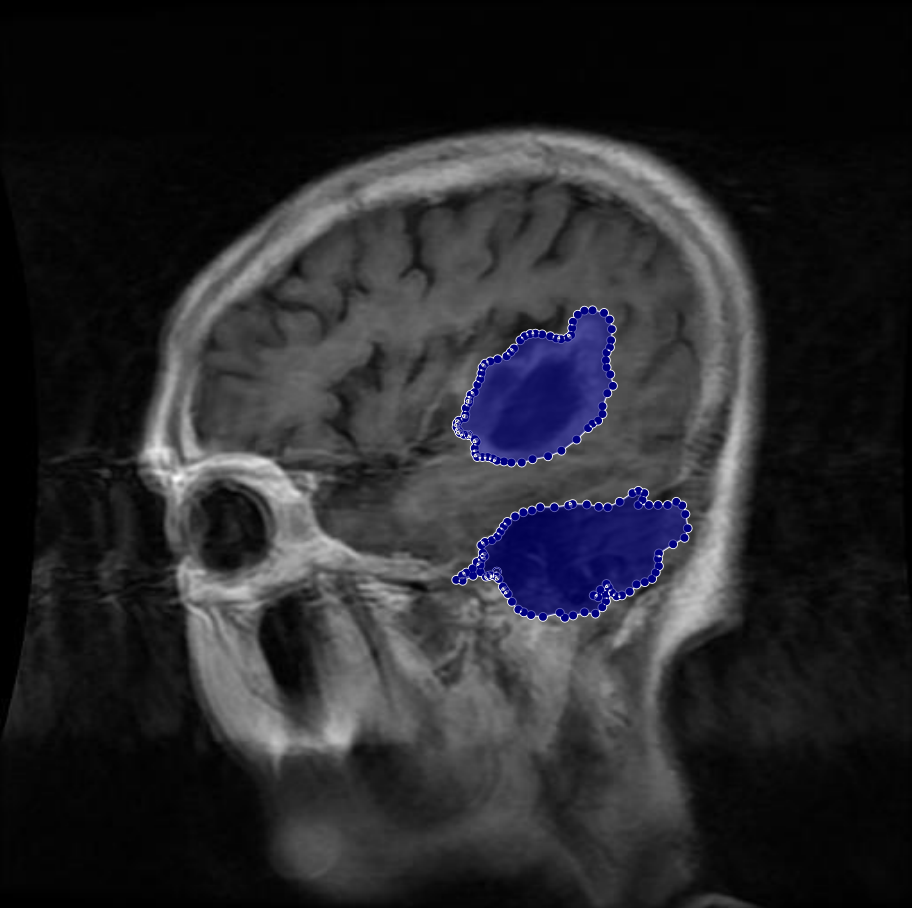

Figure 2: Samples of Meningioma segmentation across different imaging planes

Meningioma: Meningiomas arise from the meninges and are generally well‑circumscribed and homogeneous, making them easier to segment. However, their location adjacent to critical structures such as dural sinuses and cranial nerves can complicate diagnostic tasks. An example of a meningioma and its segmentation mask is presented in Figure 2, illustrating the clarity of its boundaries.